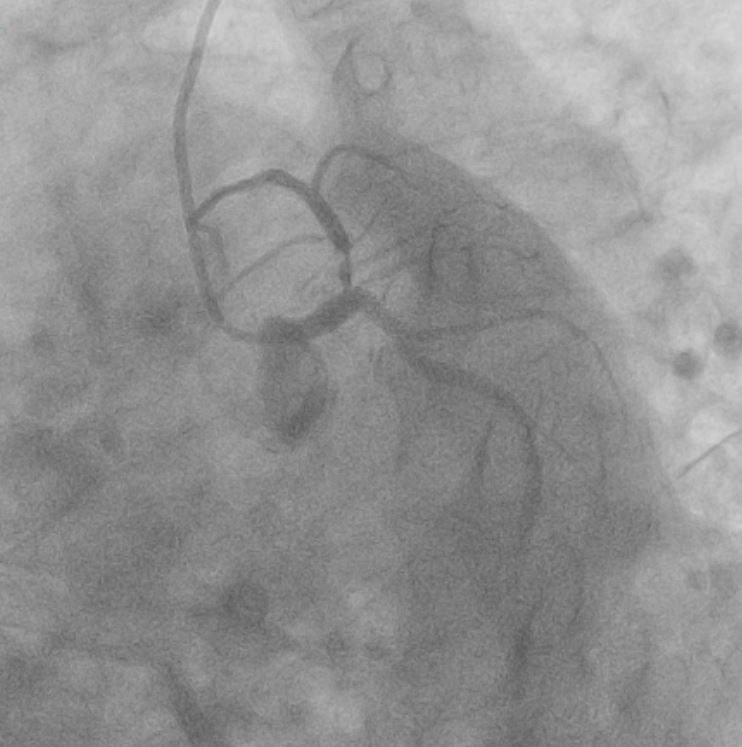

Coronary angiogram shows severe disease ostio-proximal LAD with severe calcification/calcium nodule , mild disease left circumflexsevere stenosis proximal and mid RCA -recessive

Right Radial approach, Slender 6/7Fr , EBU 3.5 7FR changedto EBU 3.0 7FR Sion blue to LCX, Run-through floppy to LAD IVUS run to LAD Fibro calcified lesion ostial LAD - calcium arc 180 degrees with calcium nodule, ostial LAD 3.48mm2 , tightest proximal LAD 2.31mm2 distallumen size 3.0mm and proximal 3.5mm and ostial 4.0mm ostial LM MLA 10.8mm Used microcatheter fine cross to LAD , Exchange with balloon trapping withRotaWireRotablator 1.5burr introduced- 2 runs high speed 180kph and2 runs at 80kph IVUS done post Rotablator - tightest proximal LAD 2.31mm2 -->3.22mm2 , ostial LAD 3.48mm2 -->4.51mm2 Predilate further NC 3.5x15mm up to 16atm Stented Synergy monorail 3.0x32mm body LM to proximal LAD at11atm with guide plus 6FRpost dilated NC 3.5x12mm up to 20atm Guiding catheter slipped out and lost the system, tried to reengage but challenging thus decided to change to right femoral puncture to use EBU3.5/7fr ,post dilate LM-LAD NC 4.0/12mm 6atmOstial LCX pinched - decided for Kissing balloon inflation and DCB LCX ostium predilated Ostial LCX 2.75x15mm up to 8atm Kissing inflation performed with NC emerge 3.5X15mm LAD, NC2.75x12mm in LCX 8atm DCB AGENT MONORAIL 2.75X15 MM 8atm 60seconds to ostial LCX last POT with NC 4.0x12mm up to 16atm IVUS done stent well opposed, Ostial LAD MSA 8.25mm2Proximal MSA 5.64mm2 TIMI III flow